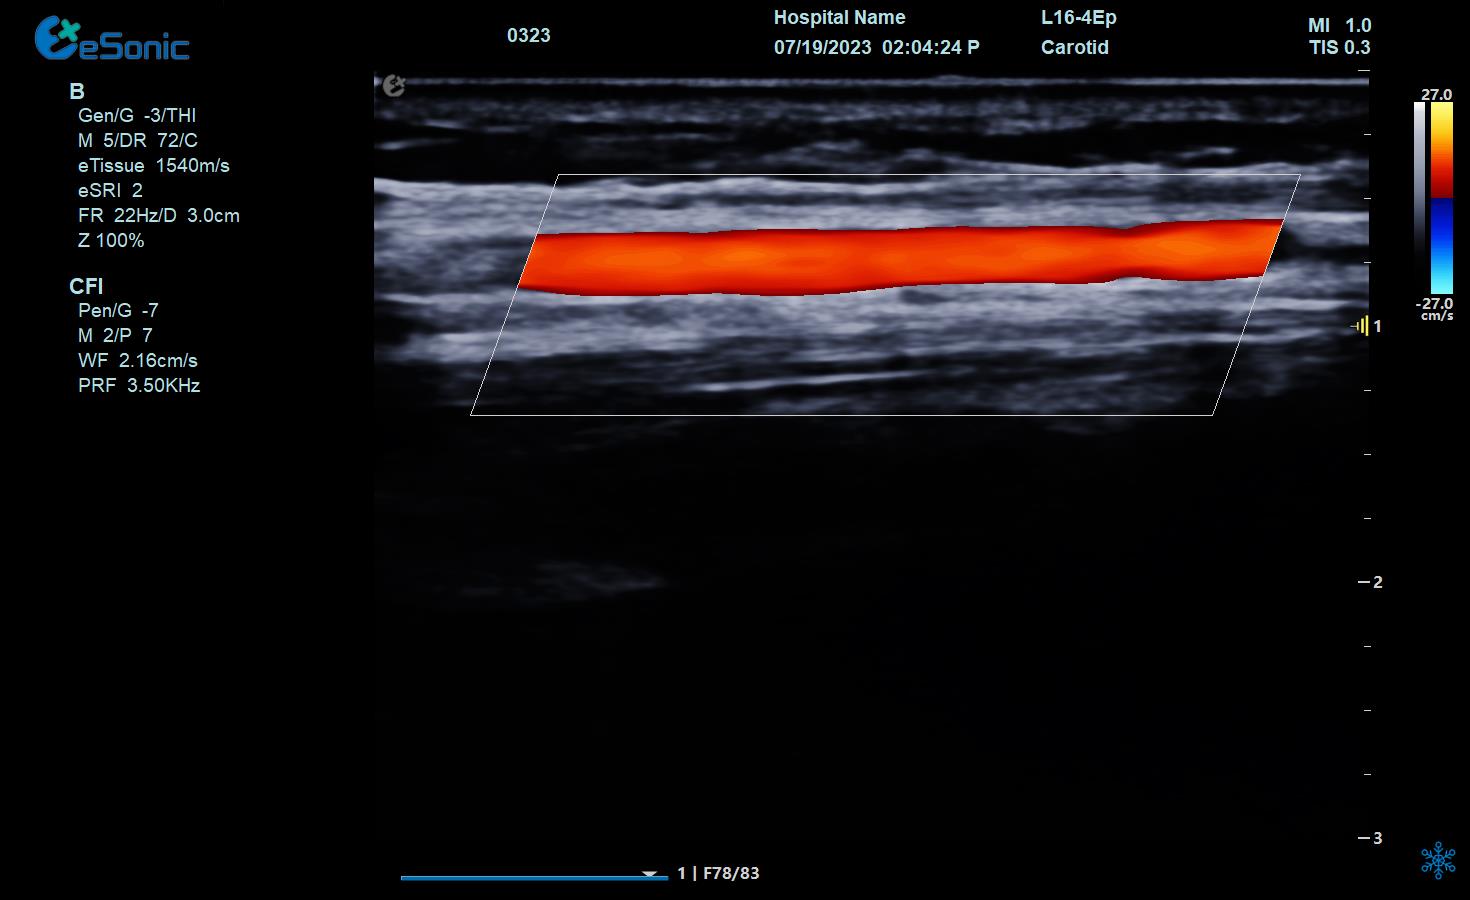

颈部血管